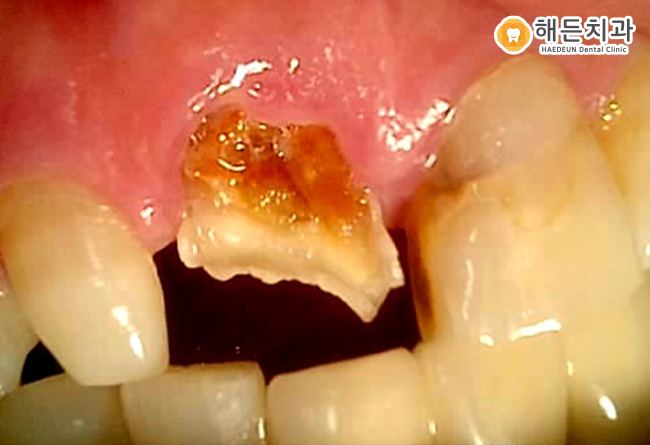

위의 환자분의 경우 보시다시피 착색도 많으며 구강관리가 전혀 되지 않았습니다.

이로 인해 신경치료 한 치아라도 염증이 재발하였으며, 흔들림이 나타나 임플란트를 진행하게 되었는데요.

잇몸 염증으로 인해 치조골이 녹아 뼈이식을 진행하고 임플란트를 식립을 진행하게 되었습니다.

발치 후 한 달 정도 잇몸상태를 확인하였고, 잇몸상태가 좋아져 당일 뼈이식과 식립이 동시에 가능하여 함께 이루어졌습니다.